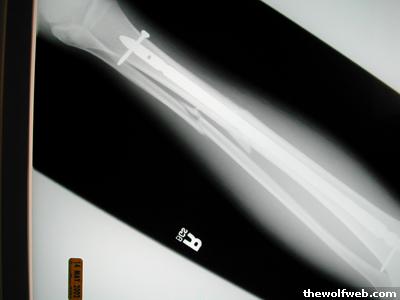

Photo Gallery » sparkydwp » postop2

postop2